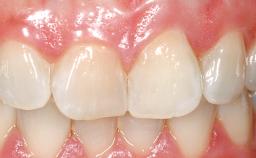

A 39-year-old male patient presented with a chief complaint of discomfort and gingival discoloration around his maxillary left central incisor. He was in good general health and was a non-smoker. His past dental history was significant because of the traumatic fracture of tooth 21 in a sporting accident at age 13. Initial dental treatment included endodontic therapy and a full-coverage restoration. The patient became symptomatic 5 years later, when structural failure of the tooth resulted in the dislodgment of the crown. Endodontic retreatment, apical surgery, and post-and-core restoration were performed.

Soft Tissue Grafting Simultaneous

Prosthesis Type FDP

Soft Tissue Contour and Volume Slightly compromised